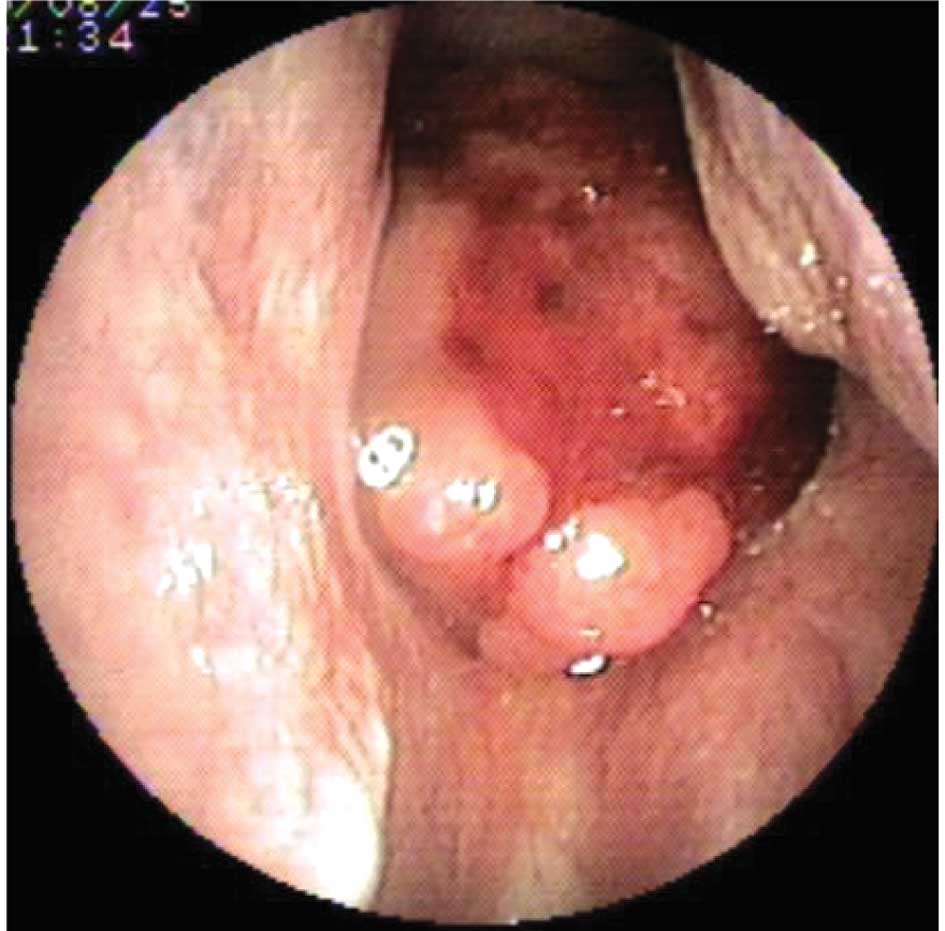

Nasopharyngeal carcinoma

Three days following surgery, the patient

experienced epistaxis and was sent for an endoscopic nasopharyngeal

examination. A mass with active mucosal bleeding was found and

biopsied (Fig. 2). Histopathology

revealed a non-keratinizing undifferentiated carcinoma. MRI showed

an enlarged lymph node in region II of the right neck and an

invasive mass in the parapharyngeal space (Fig. 3A and B). The patient was diagnosed

with nasopharyngeal carcinoma, T2N1M0/stage II (UICC, 2002).